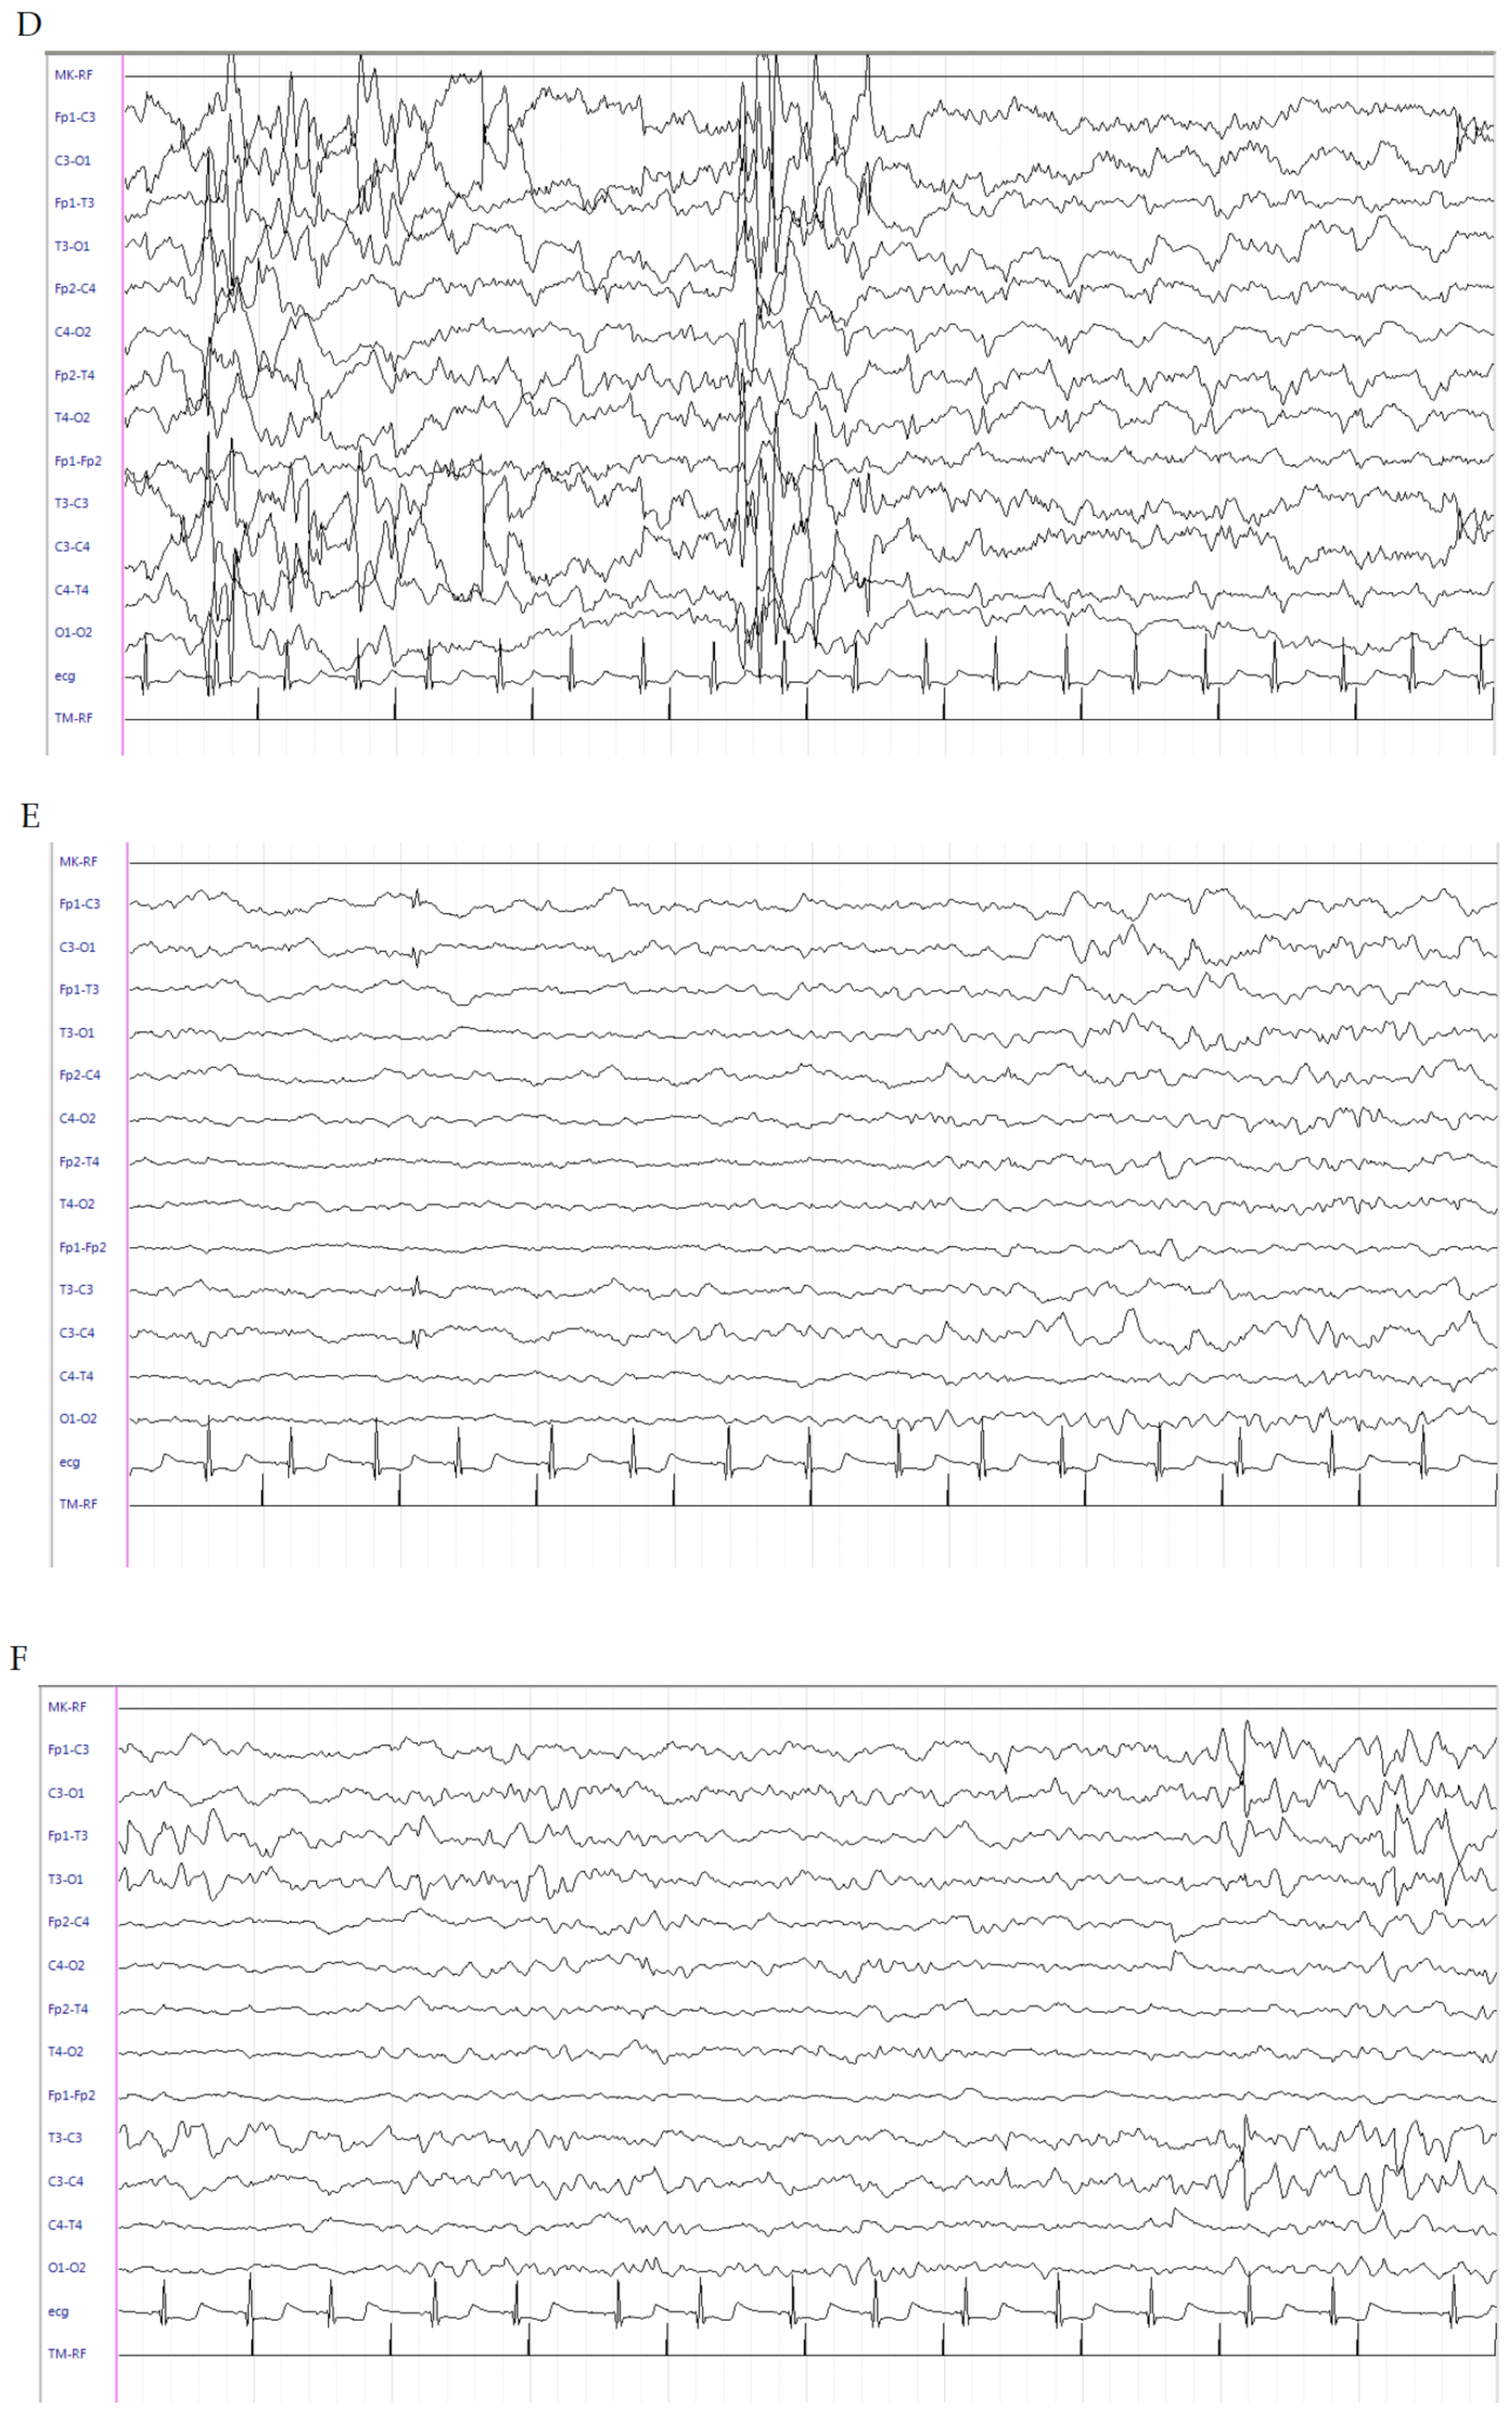

2.1. Patient 1

2.2. Patient 2

2.3. Patient 3